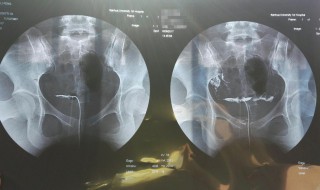

1、造影检查:对于缺乏自然对比的结构或器官,可将密度高于或低于该结构或器官的物质引入器官内或共用间隙,使之产生对比以显影即为造影检查,被引入的物质称为造影剂或对比剂。大部分对比剂中含有碘,碘过敏者应注意。

2、造影检查是将一种比人体密度高或低的物质导入到人体内要检查的部位,人工地造成要检查部位密度差异,以构成对比,达到诊断的目的。造影检查前,患者要做必要的准备。